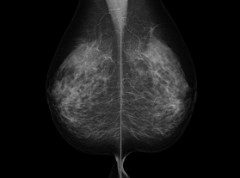

これって…ネコマルさんのお胸じゃないの?ww

これじゃ~

左のおっぱいがちょっと重力に負けかかってますね

そろそろちゃんとした検診を受けなきゃです

レントゲンは片方づつ撮るの?

綺麗な形ですね

影とか無かったですか?